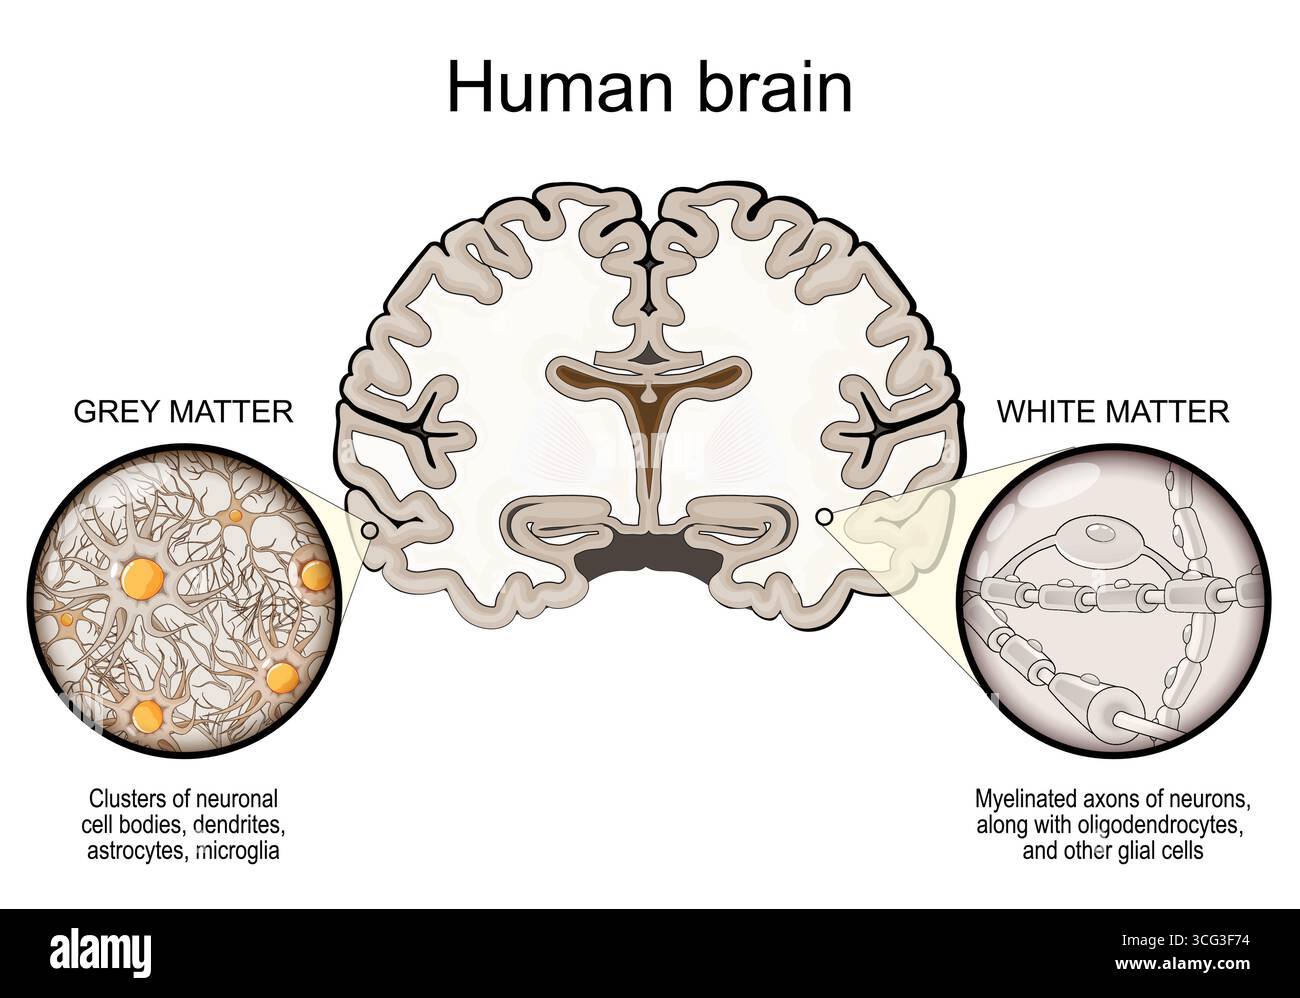

RF2XHY7B8–Anatomia cerebrale. Materia bianca e materia grigia. Corteccia cerebrale e ventricoli cerebrali con liquido cerebrospinale. Sezione trasversale di una vista frontale del cervello umano

RF3CG3F74–Anatomia del cervello umano. Sezione trasversale del cervello con materia grigia e materia bianca. Primo piano di assoni mielinati di neuroni, oligodendrociti, cellule gliali,